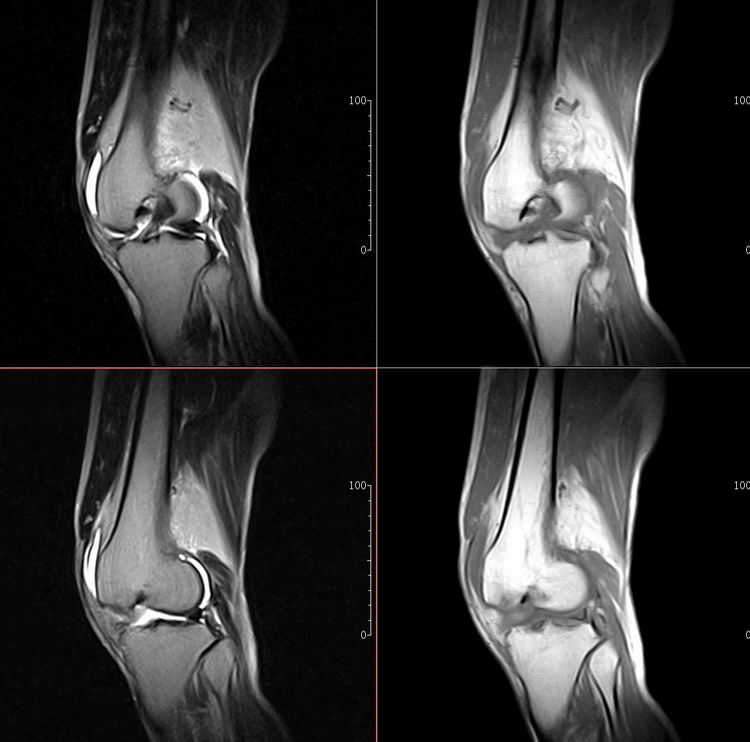

标题: MRI1910:M 687Y。近日因外伤疼痛,而就诊。

m 687y。近日因外伤疼痛,而就诊。有外侧副韧带损伤吗??因片子较差各位请包涵。

这算什么位置呢?矢状位?冠状位?

关节退行性变伴股骨外髁关节面下囊肿,不除外剥脱性骨软骨炎.关节积液,髌骨软化症

体位不标准。关节退变伴关节积液。

1)膝关节骨质退行性改变。

2)由于体位的关系不能确定有外侧副韧带的损伤。

关节退变伴关节积液,外侧副韧带的损伤

关节积液,外侧副韧带的损伤